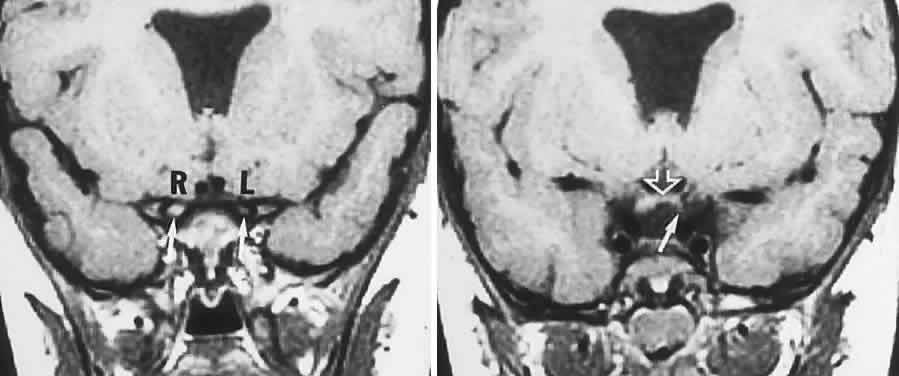

Microangiopathy of the brain, retina, and inner ear (Susac's syndrome) is a rare disorder predominantly affecting women of child-bearing age, but without a specific origin or systemic manifestations. An immune or coagulopathic background is unproved. Patients present with the following: vision loss due to branch retinal arteriolar occlusions with vessel hyperfluorescence on fluorescein angiography, and delayed leakage; hearing loss; multiple CNS infarctions.113 Efficacy of treatment with corticosteroids and immunosuppressive agents is uncertain, but hyperbaric oxygenation has been beneficial in a single case, with rapid visual improvement.114